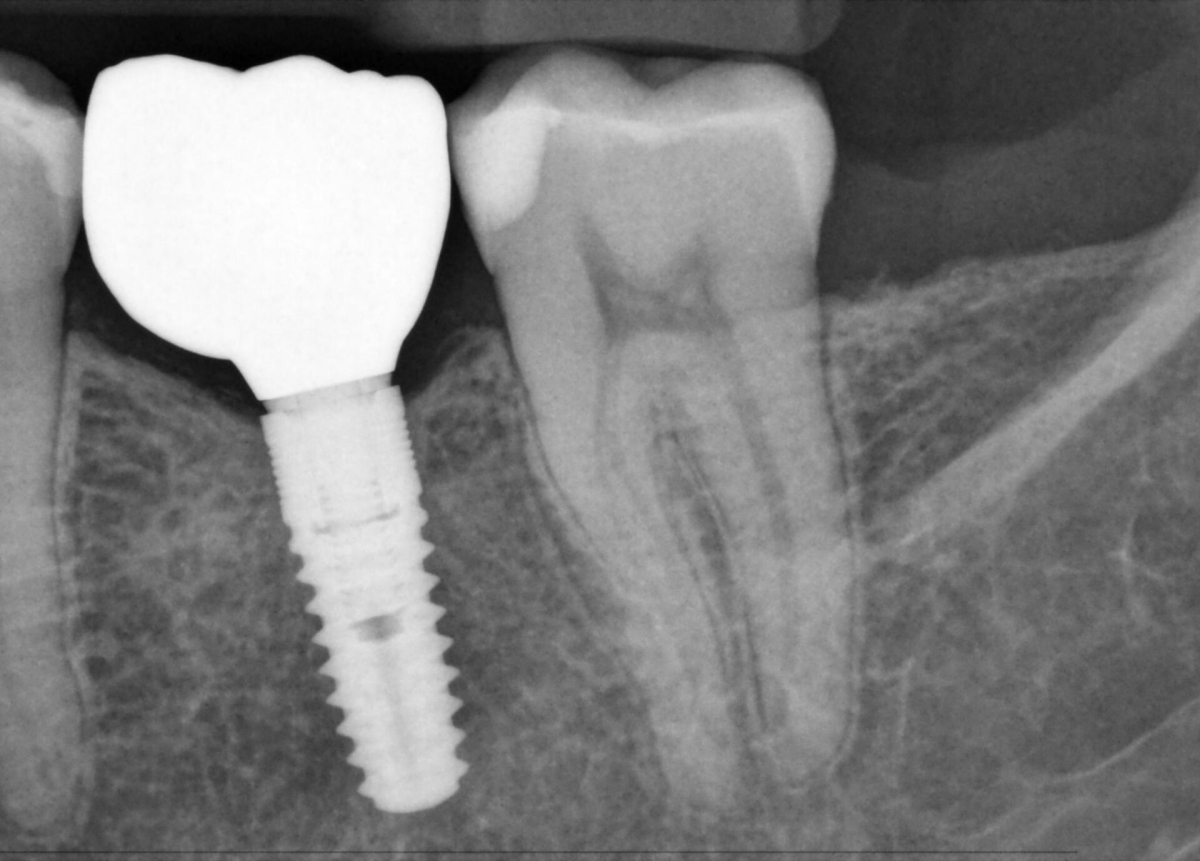

Imágenes superiores para cuidado óptimo del paciente

Los sensores intraorales de Dentsply Sirona proporcionan calidad de imagen de vanguardia que apoya el diagnóstico preciso del tratamiento y visión clara de la situación clínica. Respaldado por elecciones expansivas del sistema, mejora de filtro de imagen y servicio de vanguardia y personal de apoyo, los sensores intraorales Xios ofrecen varias posibilidades para su consultorio - brindándole beneficio a usted y sus pacientes.